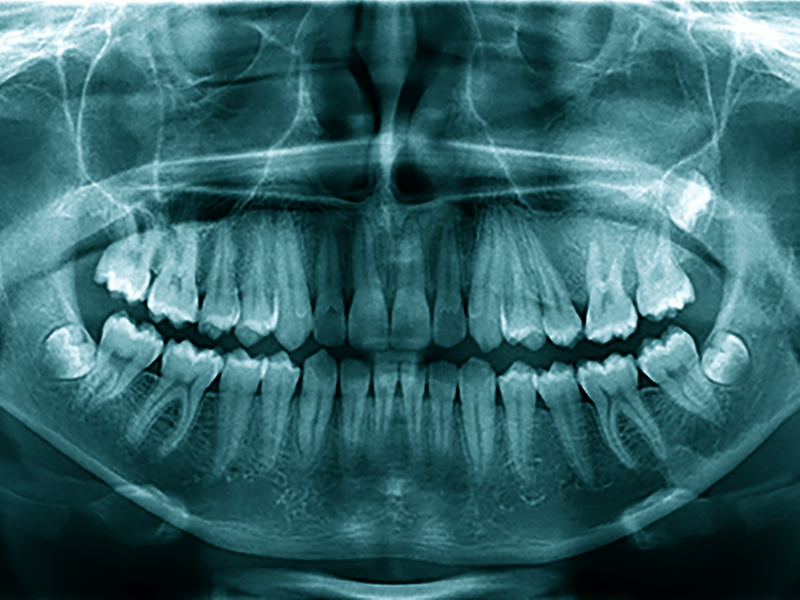

Im Orthopantomogramm (OPG) von 2020 (Abbildung 1) zeigte sich eine Divergenz zwischen den Zahnwurzeln 25 und 26 bei interdentaler homogener Verschattung mit Ausdehnung innerhalb des Processus alveolaris der Maxilla in Höhe 25 bis 27 sowie Fortsetzung nach kranial mit Projektion auf den Sinus maxillaris links. Nebenbefundlich waren die Weisheitszähne 28, 38 und 48 raumbeengt angelegt. Im OPG von 2017 (Abbildung 2) hatte schon eine angedeutete Divergenz der Wurzeln 25 und 26 ohne weitere Hinweise auf das sich später entwickelnde Bild bestanden, möglicherweise der Punkt, von dem die Erkrankung ihren Ausgang nahm. Hauszahnärztlich waren Erkrankungen der Zähne und des Parodonts im Vorfeld ausgeschlossen worden.